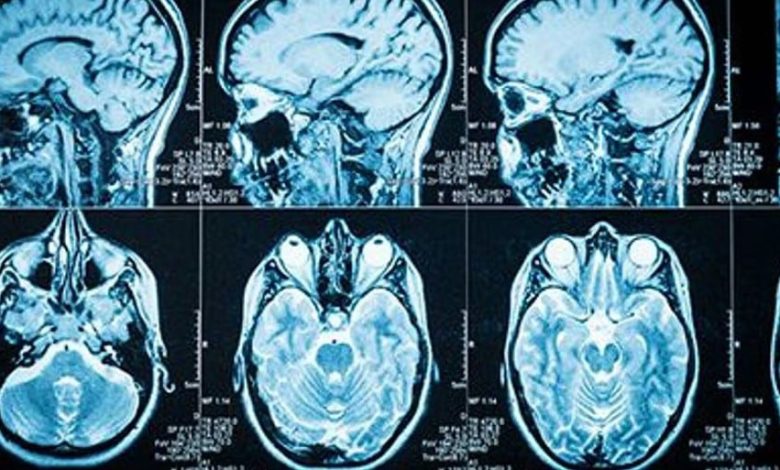

Different Types of Brain Tumors: What They Are, How They Present and What To Expect – BlackDoctor.org